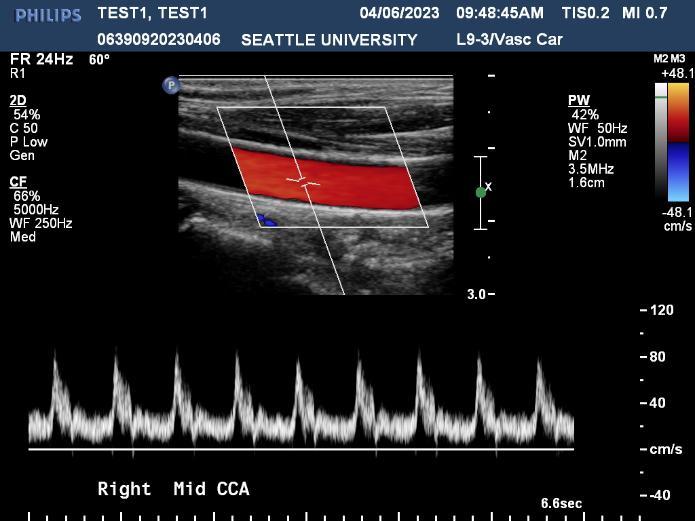

Ultrasound is a non-invasive diagnostic tool that uses high-frequency sound waves to propagate images of organs and tissues within the body. The Diagnostic Ultrasound program at Seattle University offers three distinctive track specializations in General (abdomen extended, OB/GYN) Vascular and Cardiac sonography.